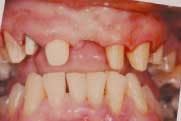

Local anesthetic (3.5 carpules of 2 percent Septocaine) was administered. Teeth Nos. 6, 7, 8, 10, and 11 were prepared with a variety of coarse diamonds. A chamfer finish line was created using a Brasseler No. 5847KR black diamond. This diamond produces a smooth, consistent margin (Figure 3).